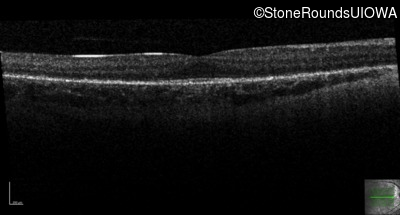

Optical Coherence Tomography - Right - 10/16 sc

Exemplar / OCT Stack